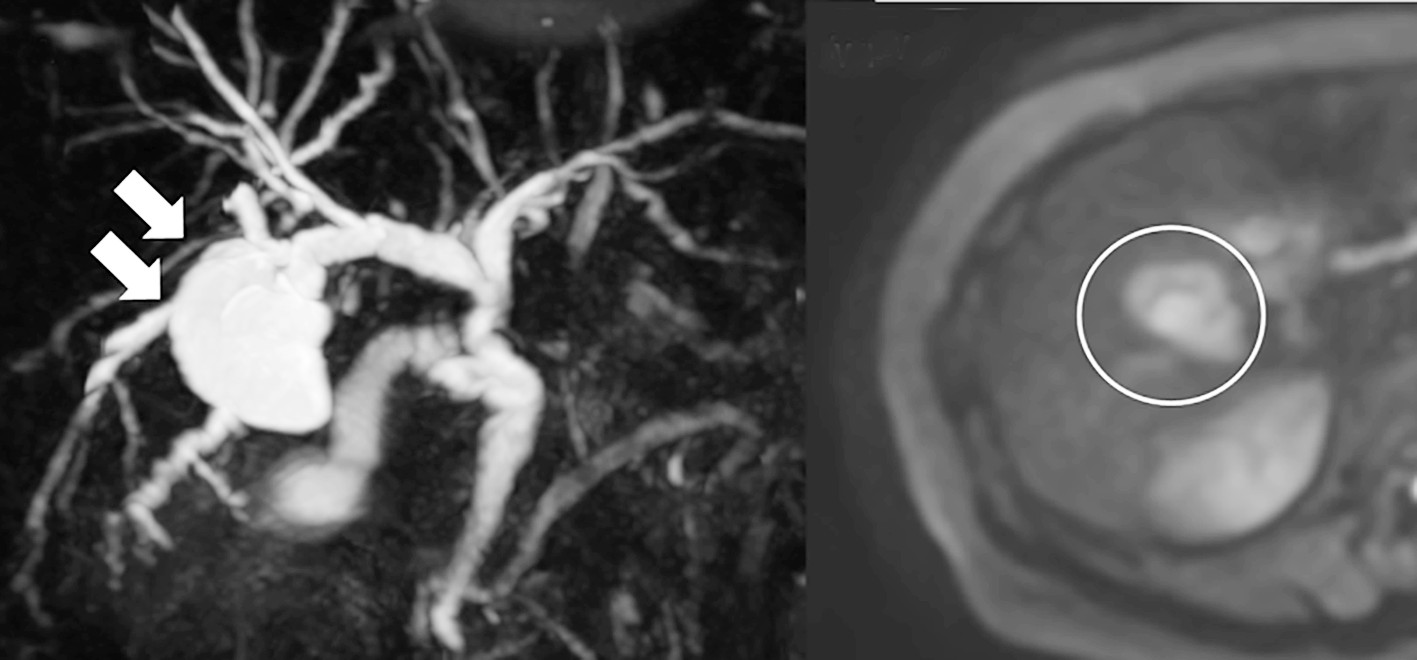

Abdominal ultrasonography identified a space-occupying lesion at liver segments 5 and 6, measuring 30 × 30 mm in diameter, with a mural nodule. Dynamic computed tomography indicated that the mural nodule inside the cyst was slightly enhanced during the early phase; this enhancement was prolonged during the delayed phase (fig. 1 a-c). Magnetic resonance cholangiopancreatography revealed that the tumor was connected to the biliary duct of segment 5 (fig. 2 a, b). Endoscopic retrograde cholangiopancreatography revealed that the intrahepatic bile duct was dilated owing to mucin produced by the tumor and that the tumor was connected to segment 5 of the biliary duct

Figure 2 - Magnetic resonance cholangiopancreatography (MRCP). (a): MRCP shows a 30-mm multifocal cyst at segment 5 with a liquid reservoir inside. (b): Diffusion-weighted image (DWI) reveals a pale abnormal signal from the mural nodule within the cyst